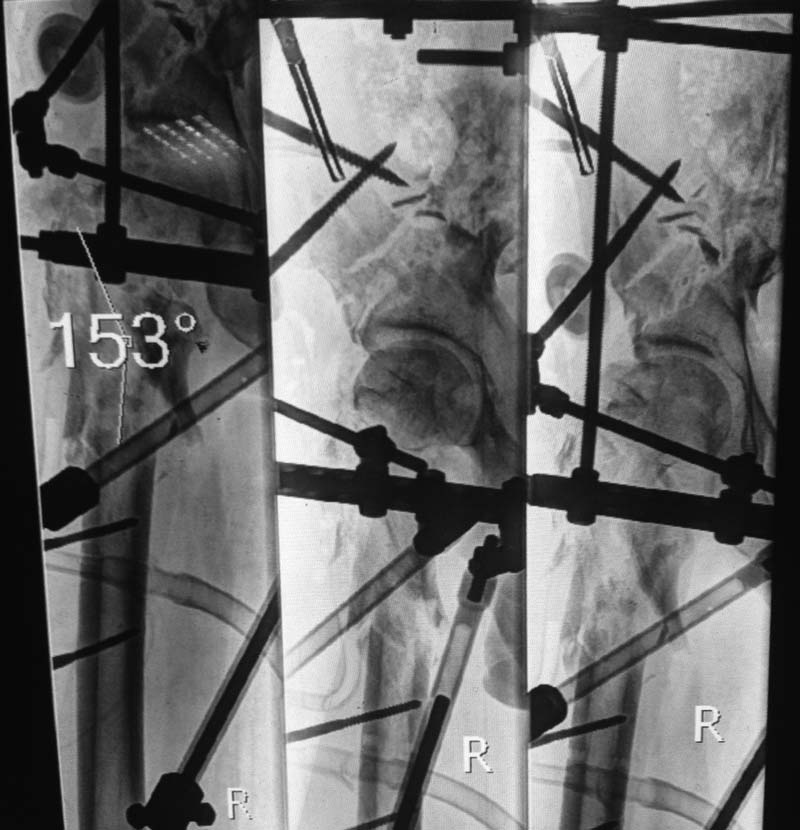

Уважаемые коллеги! Лечим пациента с огнестрельным переломом правой подвздошной кости и проксимального отдела бедра. После ранения развилось нагноение костно-мышечной раны в области проксимального отдела бедренной кости, которое после нескольких ХО купировано, раны зажили. Все переломы фиксированы в аппаратах. Планируем выполнить остеосинтез проксимального отдела бедра каким-нибудь цефаломедулляром. Хотел бы услышать мнение коллег и советы по данному случаю, в особенности Александра Николаевича. Спасибо!

Такое ощущение, хотя по этим снимкам сложно судить, что стояние отломков приемлемое. Может не спешить с заменой метода фиксации. Учитывая перелом таза все равно с нагрузкой спешить нельзя. Если есть другие снимки и доводы за хирургическое вмешательство, выложите, пожалуйста.

Вполне можно действительно сделать гвоздиком с цементным покрытием. Какой конкретно аспект требует обсуждения?

реально ли будет "поймать" головку винтами при данной картинке? Что , возможно, будет с такой шейкой-головкой дальше? Гвоздь в мантии. А шеечнные винты?

Александр Николаевич, интересую особенности репозиции и установки стержня в условиях отсутствия вертельной области как таковой.